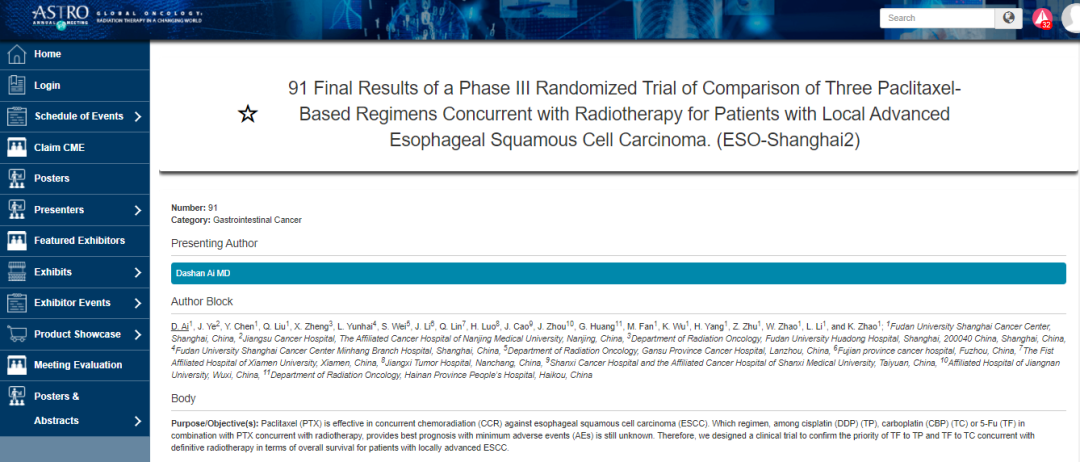

食管癌非手术治疗的化疗模式探索赵快乐教授:美国肿瘤放射治疗协助组(Radiation Therapy Oncology Group,RTOG)设计的RTOG850...

食管癌在中国和全世界都是高发的恶性肿瘤之一,传统治疗手段对食管癌的总体疗效不尽如人意。近年来,放疗与免疫治疗在局部晚期和晚期食管癌中不断取得突破。在2020 CS...